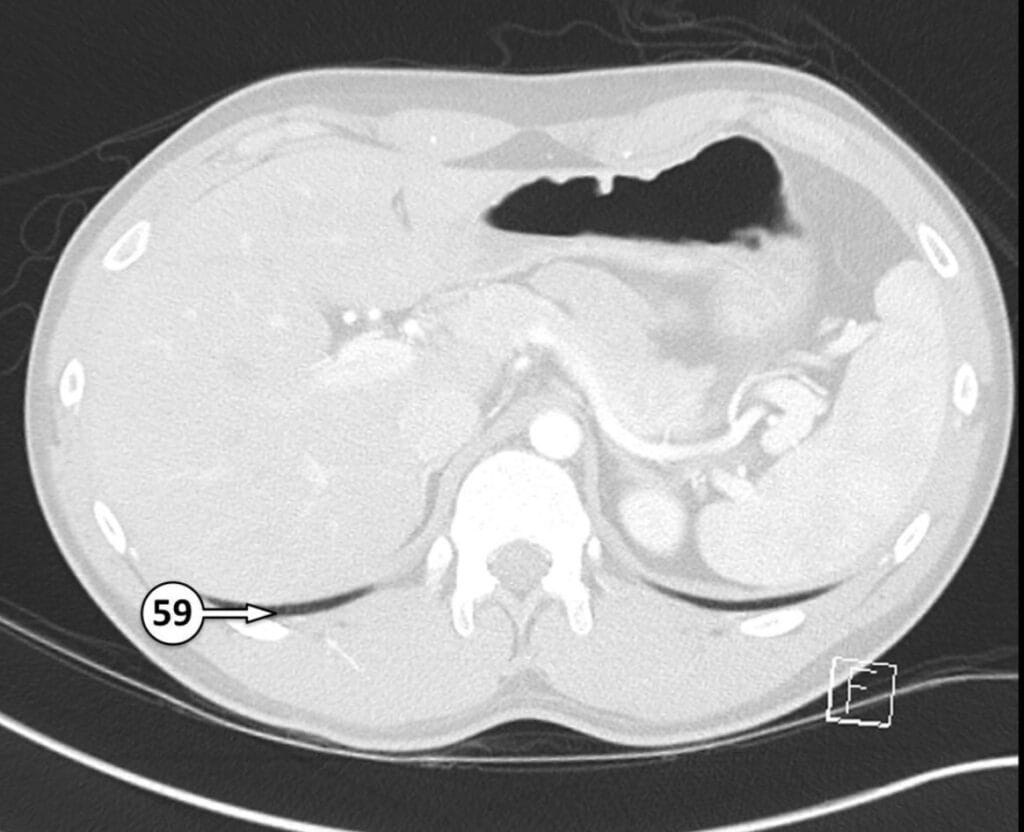

59. posterior costophrenic recess